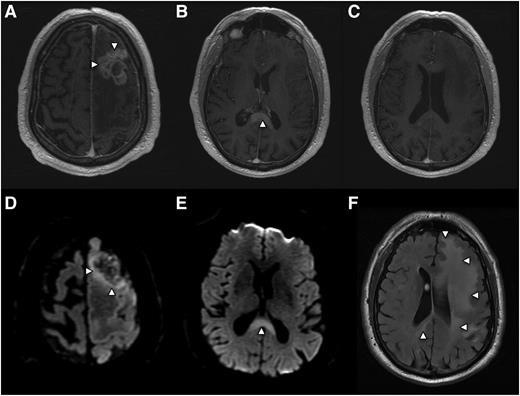

While approximately 50% of PCNSL tumors in immunocompetent patients present as a solitary enhancing brain lesion on T1-weighted MRI, ∼25% of tumors at baseline are associated with a separate, nonenhancing lesion that is hyperintense on T2/FLAIR (fluid attenuated inversion recovery)-weighted imaging at a locus that is distinct from the enhancing lesion(s).9 This observation is consistent with the fact that lymphomatous dissemination in the brain may occur in the absence of contrast enhancement on MRI (Figure 2).

PCNSL is a highly infiltrative disease, particularly at relapse, whereupon the majority of lesions are multifocal and present at sites distinct from the focus of disease presentation. Histopathologic analysis of PCNSL supports at least 2 patterns of tumor dissemination. In one, an angiotropic growth pattern, lymphoma cells appear to coopt existing brain vasculature and migrate in the perivascular (Virchow-Robin) space. This invasive phenotype disrupts the blood-brain barrier and enables radiographic detection of lesions via pathologic contrast enhancement. A second pattern is direct invasion along nerve roots, such as the optic nerve, along white matter tracks such as corpus callosum, or into the meningeal space. (Figure 3). Common patterns of relapse occur within the vitreoretinal compartment and subependymal growth into the periventricular space, leading to spread within CSF pathways. (Figure 4).

Radiographic presentation of multifocal PCNSL, characterized by distinct MRI sequences. (A) T1 postgadolinium image demonstrates an enhancing mass involving the left frontal lobe (arrows) with central necrosis and surrounding vasogenic edema. On spectroscopy the mass demonstrated increased tumor metabolites, lactate, and choline (not shown). (B) An apparently isolated, second homogeneously enhancing mass (arrow) is identified inferiorly, involving splenium of the corpus callosum. (C) No enhancing foci are detected in white matter between the 2 distinct lesions. (D) Diffusion-weighted imaging demonstrates foci of reduced or restricted diffusion (arrows), suggestive of dense cellularity, in the superior aspect of the frontal mass. (E) Restricted diffusion within the enhancing lesion involving the corpus callosum, strongly suggestive of lymphoma. (F) Extensive T2/FLAIR signal hyperintensity (arrows) extending from the frontal mass posteriorly to the corpus callosal lesion, consistent with nonenhancing lymphoma dissemination involving the cerebral hemisphere.

While T2/FLAIR images may detect subclinical, nonenhancing dissemination of CNS lymphoma, confounding MRI abnormalities involving white matter are commonly elicited by the effects of chemotherapy, including HD-MTX, brain irradiation, and normal aging. For this reason there is interest in development of novel, advanced imaging approaches to noninvasively detect and provide prognostic insight into PCNSL. One approach is diffusion-weighted imaging, which measures restricted water diffusion in hypercellular tumors such as PCNSL, resulting in hyperintensity on MRI that can distinguish CNS lymphomas from less cellular tumors such as malignant gliomas. Foci of restricted diffusion may be useful to discriminate residual CNS lymphoma from benign processes, and very low diffusion coefficients have been associated with high-risk, aggressive CNS lymphoma (Figure 2).10 Other advanced imaging approaches include magnetic resonance spectroscopy and positron emission tomography (PET), each of which are capable of detecting tumor-associated Warburg metabolism.11